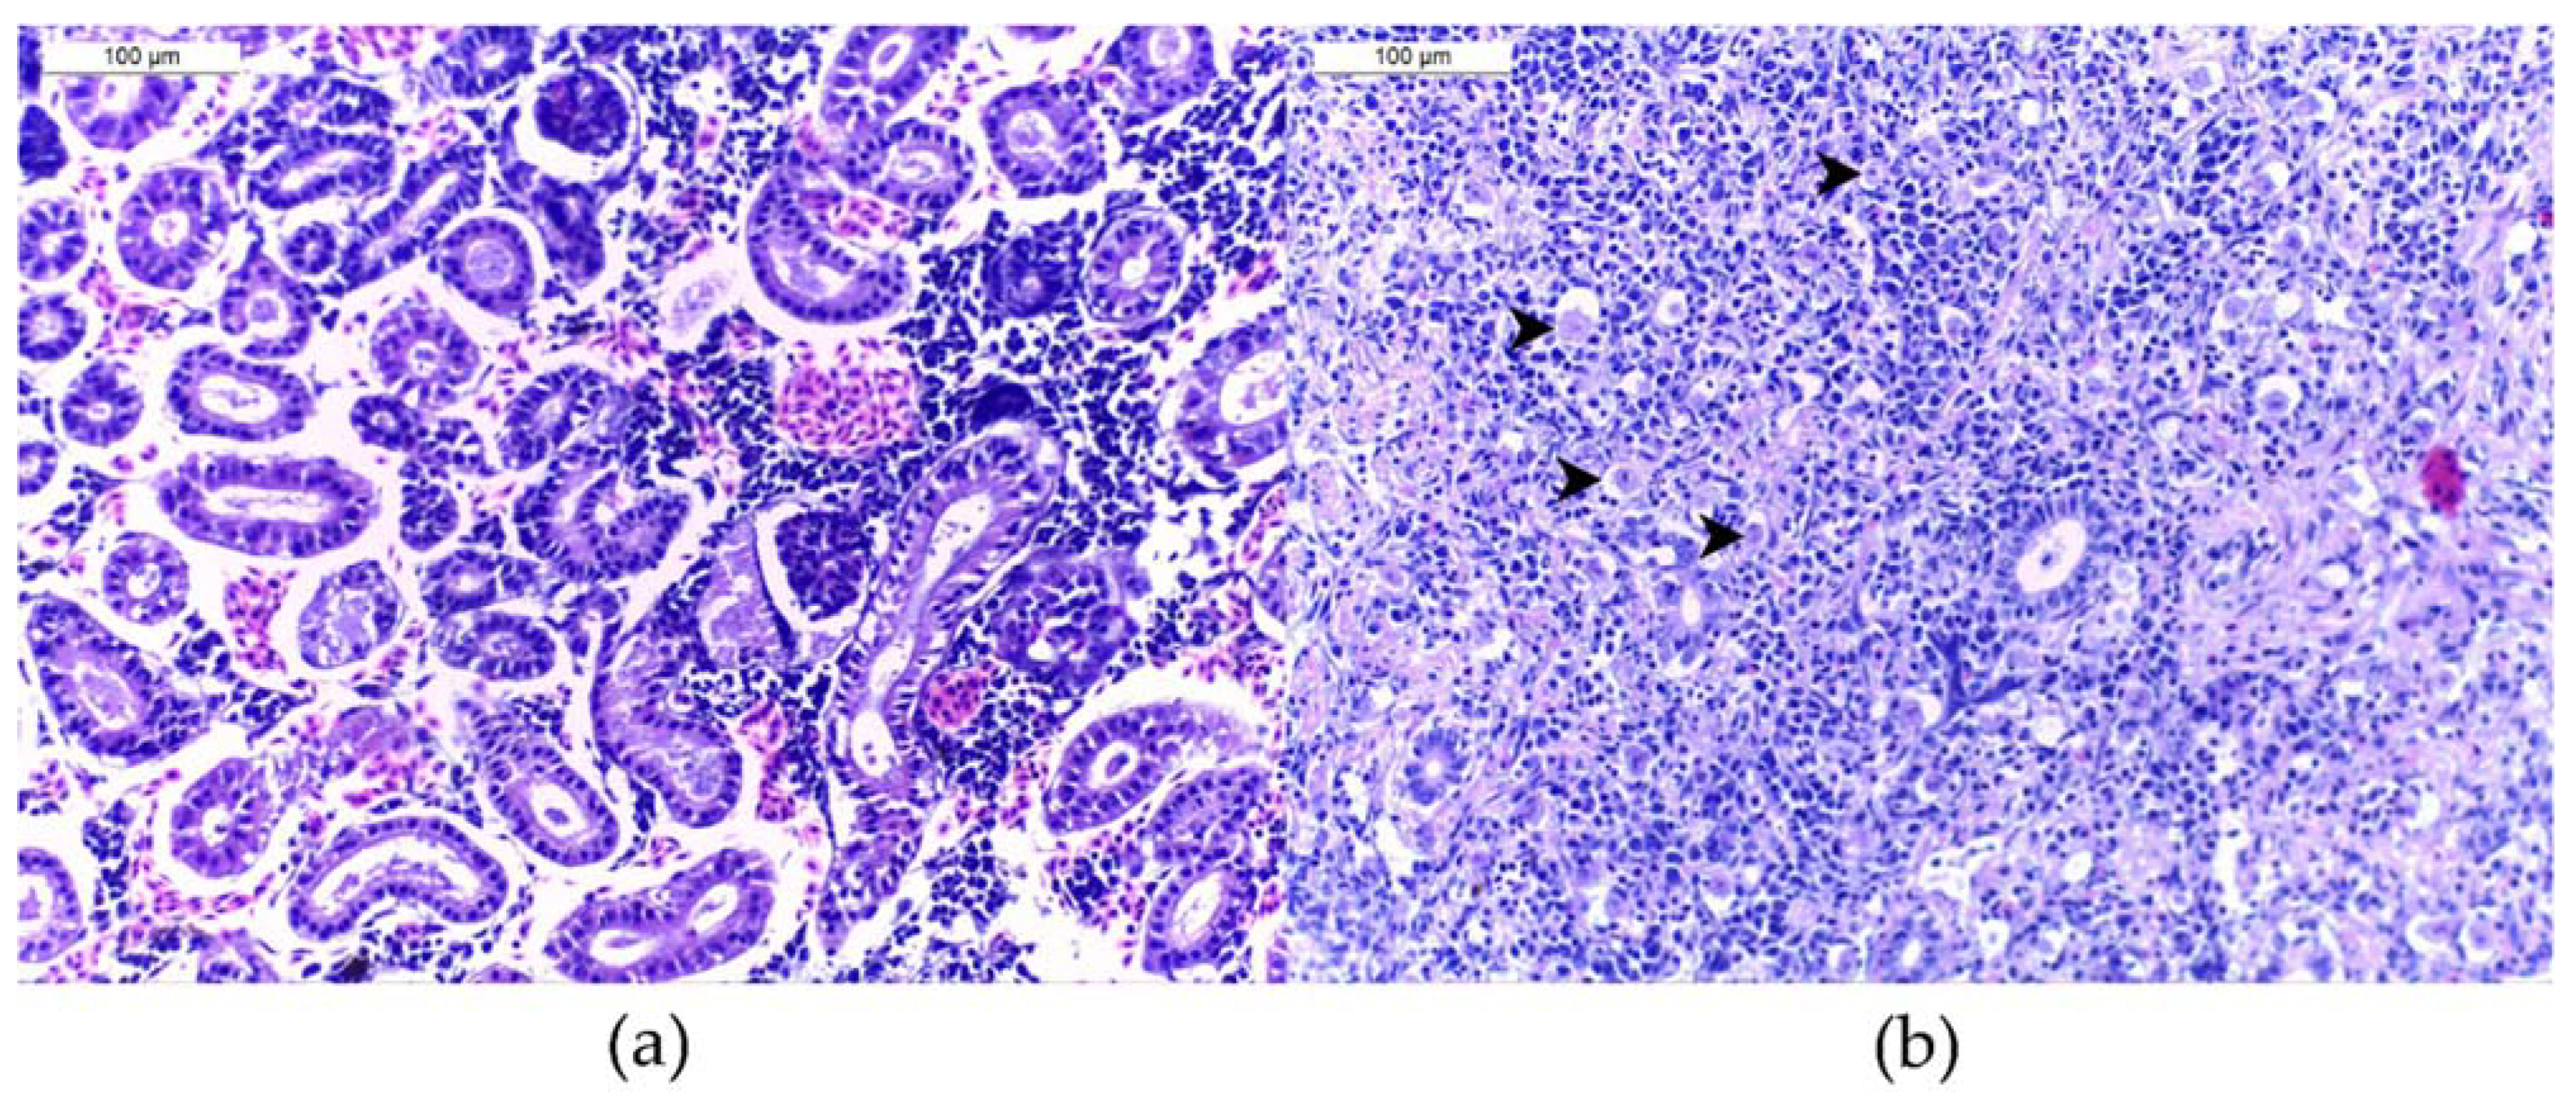

After capture, YOY were euthanized with MS222® (3-aminobenzoic acid ethyl ester, 300 mg l-1, Argent Chemical Laboratories, Redmont, WA, USA), fixed, and stored in containers containing 4% buffered formalin. Kidneys were removed from the carcasses in the laboratory, embedded in paraffin, and cut following routine histological methods. Histological slides were stained with haematoxylin and eosin. One section of a full-length kidney per animal was analyzed for the presence of T. bryosalmonae, determined through its typical cell structure (spores with four polar capsules). The infection intensity (estimation of the numbers of observed parasites) was assessed for each kidney sample with a microscope (Olympus BX41). For this purpose, a scoring system from 0 (no parasite) to 6 (at least 10 parasites per high power field with 400× magnification) was used (Figure 4) following Bettge et al. [19] and Schmidt-Posthaus et al. [22]. A fish was classified as T. bryosalmonae-infected if at least one parasite was detected in the analyzed kidney section. The infection intensity per site was obtained as the addition of infection scores divided by the number of PKD-positive fish. The percentage of T. bryosalmonae-infected fish was determined as the number of infected individuals divided by the total number of sampled fish at a particular site and time-point as described in Bush et al. [46].

Figure 4.

Histological assessment of brown trout Salmo trutta posterior kidney H&E-stained slides (a) without T. bryosalmonae parasite (infection score of 0), (b) with a severe infection (score of 6). Four parasites are pointed.